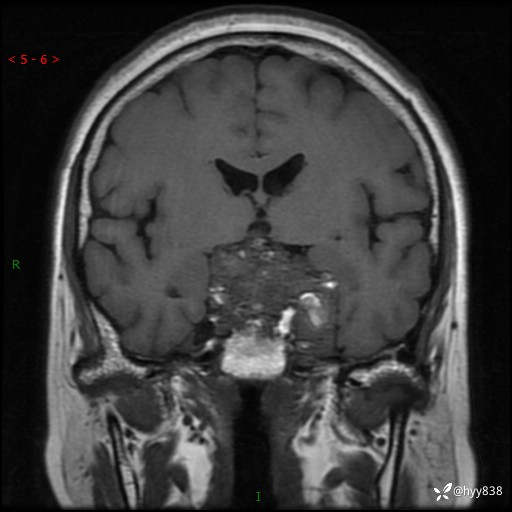

鞍区MRI平扫

T2WI